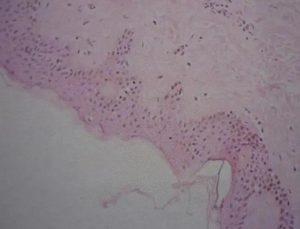

什么是结直肠癌 结直肠癌,又被称为大肠癌,是一种源自大肠上皮的恶性肿瘤,包括结肠癌和直肠癌。其中,腺癌是最常见的病理类型,只有极少数是鳞癌。在我国,直肠癌是最常见的类型,其次是结肠癌(包括乙状结肠、盲肠、升结肠、降结肠和横结肠)。 结直肠癌的发病情况 结直肠癌是全球范围内第三最常见的恶性肿瘤,也是第二最常见的致命恶性肿瘤。根据世界卫生组织癌症研究中心(WHO)的GLOBOCAN项目估计,2018年全球新发结直肠癌病例约为180万,死亡人数约为88万。 发病因素: 结直肠癌的发病与年龄、地区和性别等因素有关: 年龄:结直肠癌主要发生在40岁以上的中老年人。 性别:结肠癌的男女发病率相近,而直肠癌... 查看详情